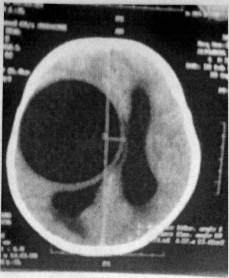

According to the computer and nuclear magnetic

tomography, the cysts are located in the white matter, mainly in the temporal

occipital lobe (Ersahin et al 1993). Of 65 patients presenting with cerebral

echinococcosis, 53 had single cyts, whilst 4 also had pulmaonary cysts and 4

had cyts in multiple locations. Single cysts were seen in the white matter of

the frontal, parietal and temporal lobes and in the ventricular cavity.